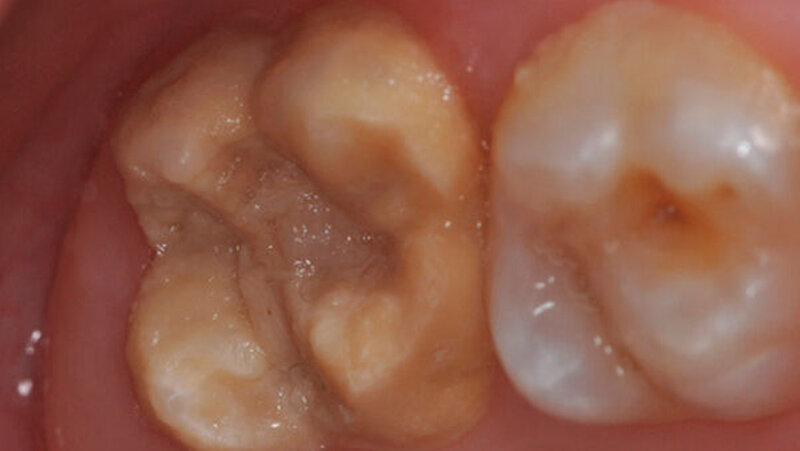

<image xmlns:ns5="http://www.w3.org/1999/xlink" seo-title="" alt-text="" aspect-ratio="16-9" ns5:href="censhare:///service/assets/asset/id/166956" ns5:role="censhare:///service/masterdata/asset_rel_typedef;key=actual."/>

Die Frontzähne sind häufig ebenfalls von MIH betroffen. Aufgrund der Farbveränderungen und dem Einbruch der Oberfläche ist die deutliche ästhetische Beeinträchtigung erkennbar. Die Kinder leiden auch psychisch mit diesem Aussehen. |

Krämer